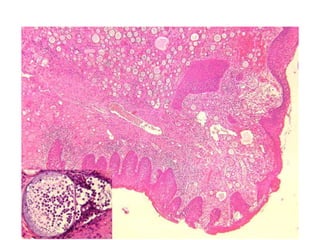

• #52 Nasal rhinosporidiosis. In the insert, globular cyst containing endospores (Haematoxylin & Eosin, 50×; in the insert, 400× . Each of these cysts represented a thick-walled sporangium containing numerous "daughter spores" in different stages of development (Fig. 1). The stroma contained

• #53 Gomori methenamine silver stain and, in the insert, periodic acid-Schiff stain (200×; in the insert, 400×).On histological examination, the lesion showed the characteristic features of the rhinosporidiosis: the polypoid fibroconnective stroma, covered by flat multi-stratified squamous epithelium, contained many globular cysts. Each of these cysts represented a thick-walled sporangium containing numerous "daughter spores" in different stages of development (Fig. 1). The stroma contained a vascular fibroconnective tissue with fibroblasts and myofibroblasts and an inflammatory infiltrate (neutrophil granulocytes, lymphocytes, plasma cells and histiocytes). Histochemical stains such as PAS, GMS (Fig. 2) and mucicarmine were used to establish the correct diagnosis of rhinosporidiosis. Morphological criteria were based on the diameter of the endospores and sporangia, respectively 5–10 μm and 50– 1000 μm. These findings made easier the distinction of Rhinosporidium seeberi from another common nasal mycosis

Case 7 • 60year old farmer • c/o – Nasal obstruction, epistaxsis since one year . • No comorbid conditions • H/O Chronic smoking , occasional ethanolic • O/E- Mass noticed in left nostril, reddish in color, strawberry like in appearence